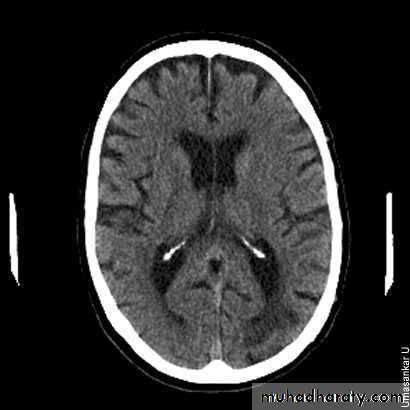

There is evidence of widening of the cortical sulci, subarachnoid spaces, and ventricular cistern denoting involutional brain changes. The occipital horn of the left lateral ventricle is noticeably dilated and associated with a large cerebral spinal fluid space, replacing brain tissue of the left occipital lobe. This may denote a sequel of a previous large infarction. There is cerebral atrophy. Cerebral atrophy is more common in patients with dementia, but it is not sensitive or specific enough to be used as a diagnostic marker for dementia. CT scans are used to exclude structural and potentially treatable causes of dementia, such as brain tumours and normal pressure hydrocephalus.